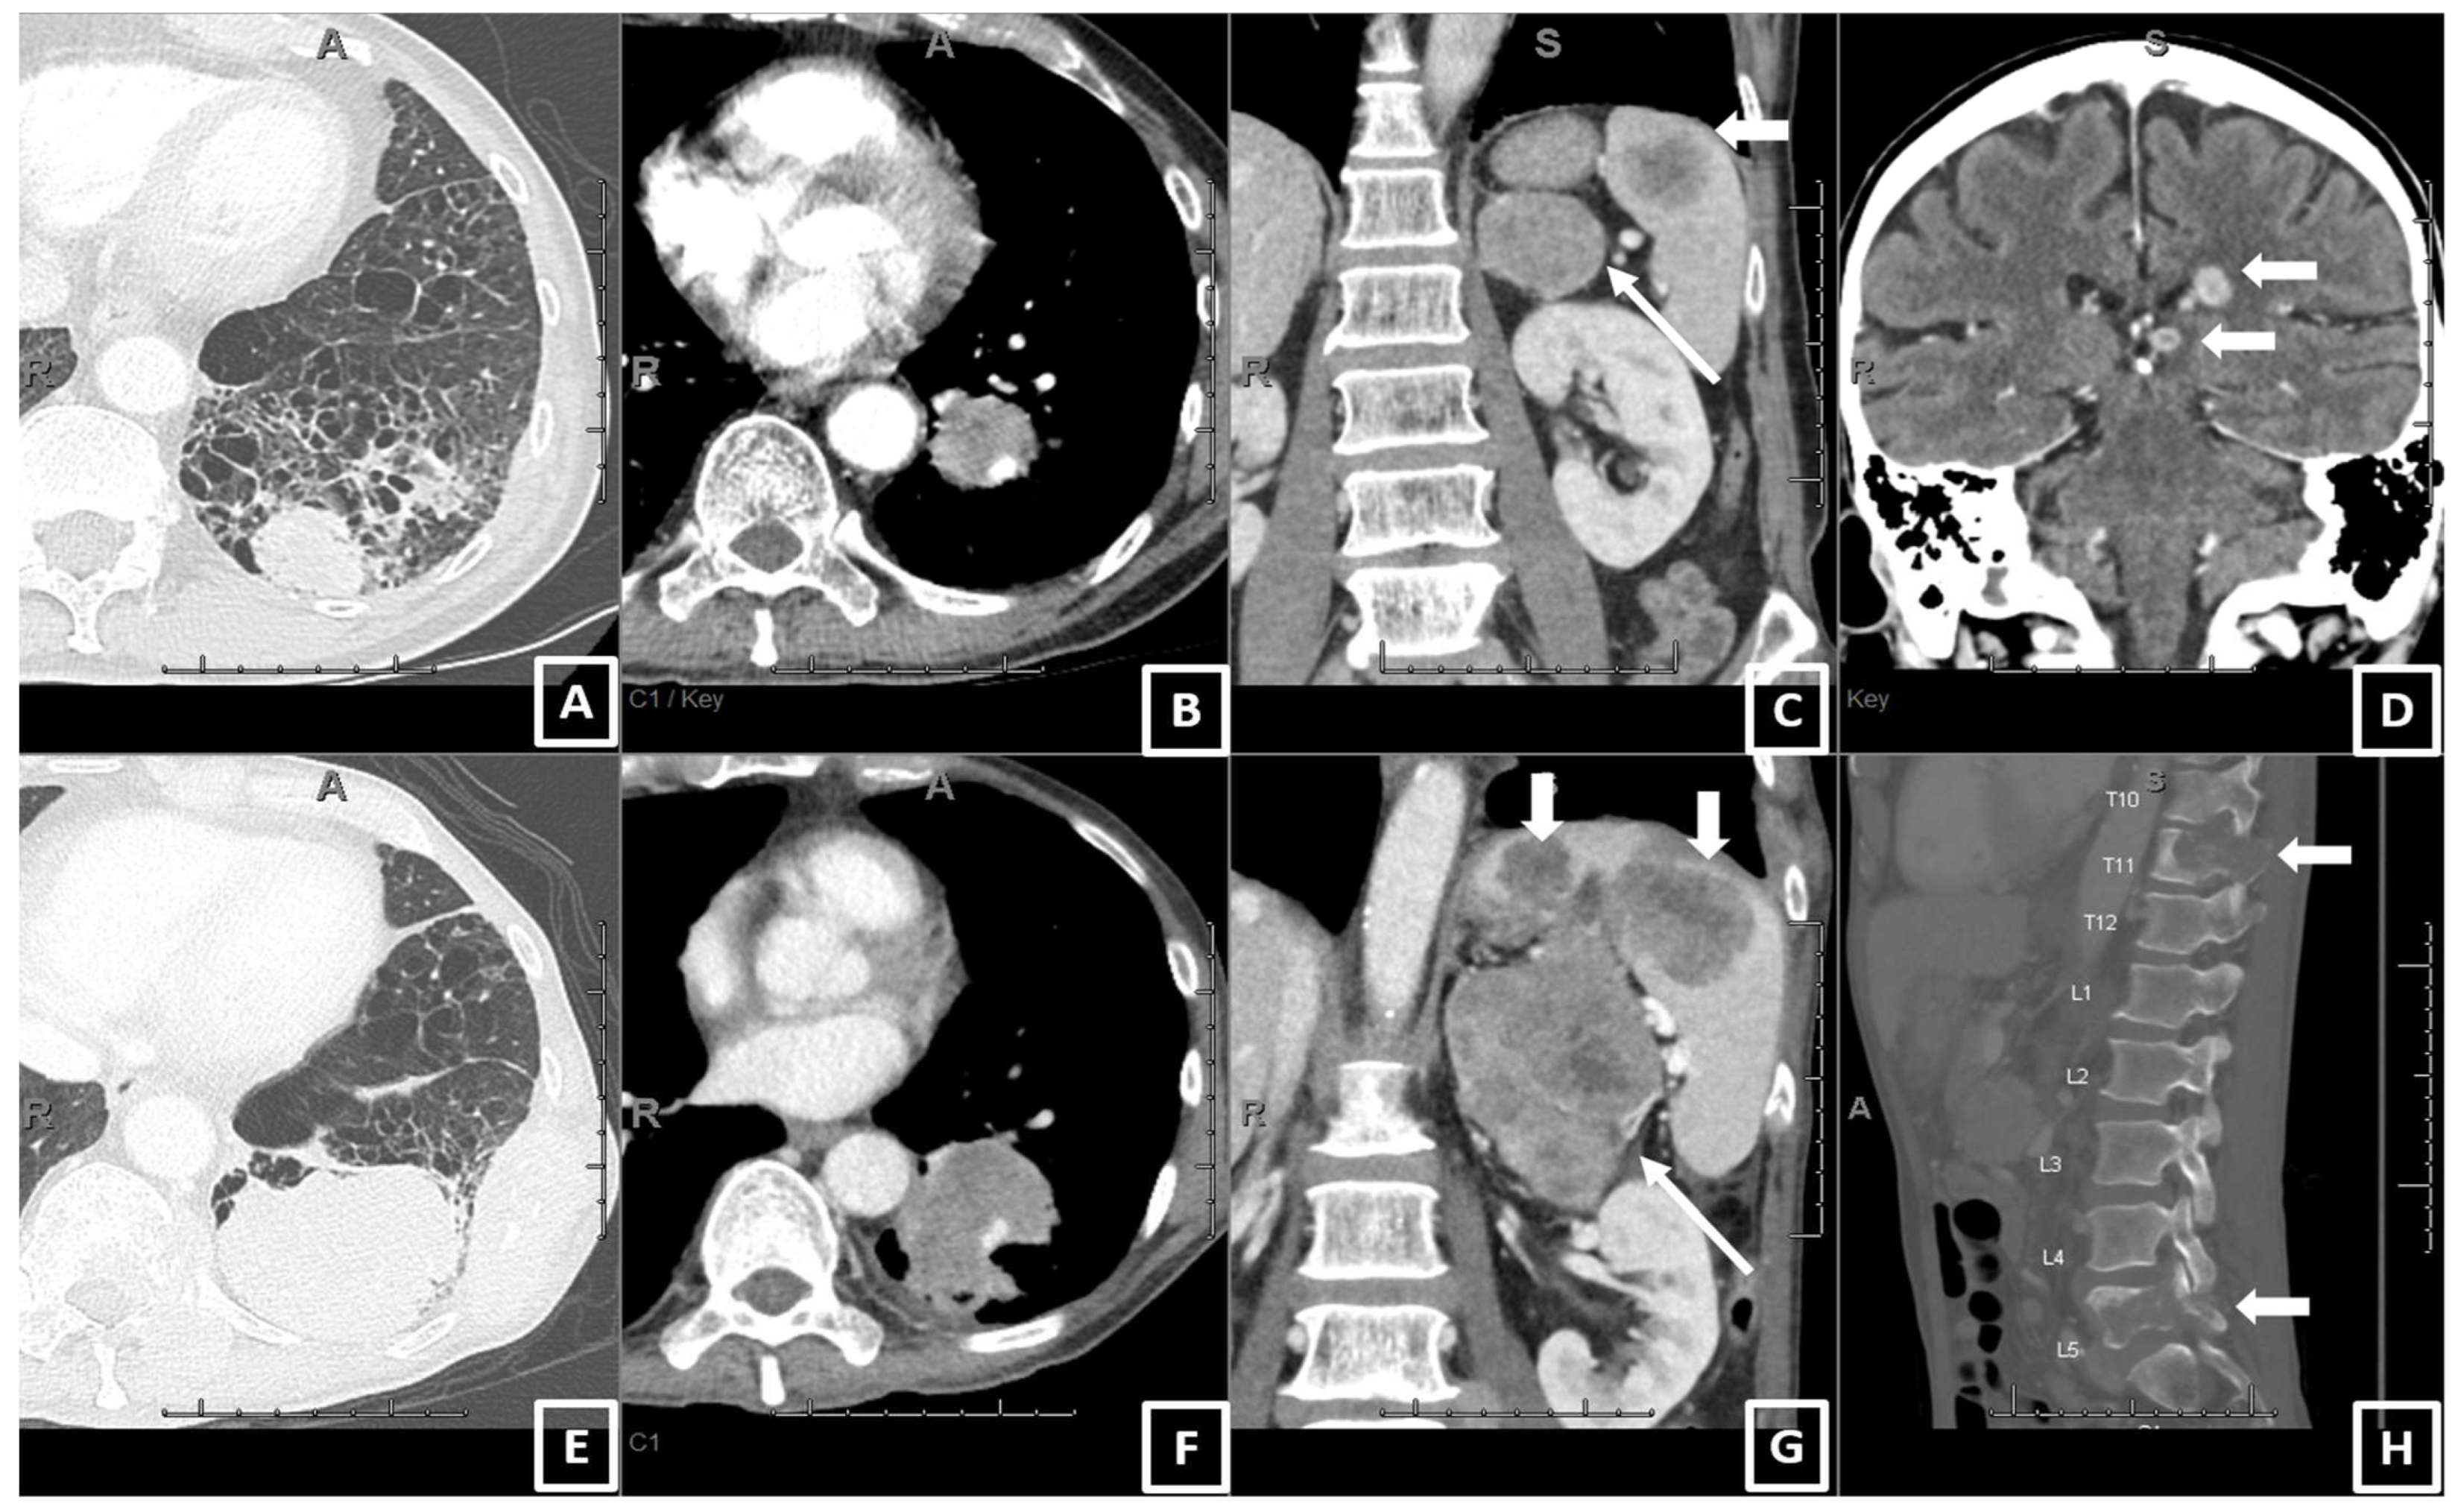

2.2. CT Scan Acquisition and Review

| On baseline CT: Number of patients with metastatic involvement in organs (n, col%) | |||||||

| Lung | 72 | 52.17 | 27 | 58.70 | 45 | 48.91 | 0.3662 |

| Lymph node | 114 | 82.61 | 42 | 91.30 | 72 | 78.26 | 0.0612 |

| Adrenal | 33 | 23.91 | 16 | 34.78 | 17 | 18.48 | 0.0554 |

| Liver | 16 | 11.59 | 10 | 21.74 | 6 | 6.52 | 0.0119 * |

| Bone | 48 | 34.78 | 26 | 56.52 | 22 | 23.91 | 0.0003 * |

| Brain 3 | 21 | 15.22 | 7 | 15.22 | 14 | 15.22 | 1.0000 |

| Pleura 4 | 43 | 31.16 | 18 | 39.13 | 25 | 27.17 | 0.1775 |